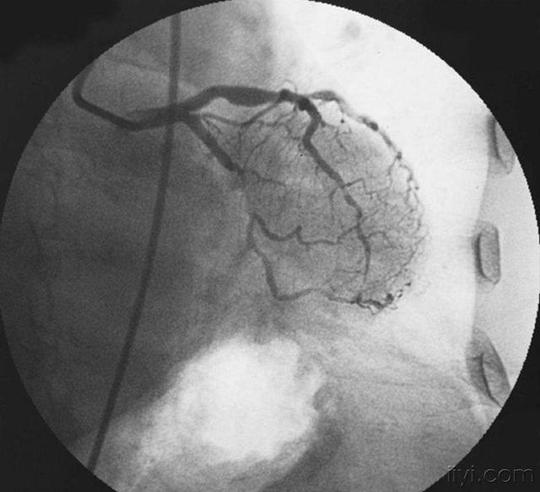

揭秘手术台丨冠脉造影原来是这么做的!

冠状动脉造影术

【医学科普】带你一起进入冠脉造影和心脏支架植入现场

冠状动脉造影

(冠状动脉造影检查)

心脏造影检查血管堵塞多少做支架

【专病专讲】冠心病之冠脉造影检查

得了冠心病,到底做心脏造影还是cta,了解这些

冠脉造影医保报销比例冠县社保局【心科普】为什么要做冠脉造影检查